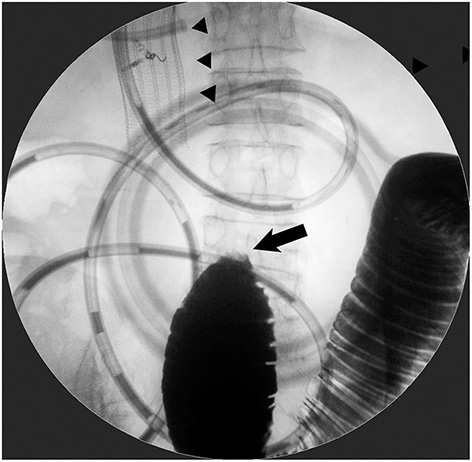

Figure 2

Patient with the coexistence of distal small-bowel obstruction. Stent placement for D2 obstruction from gallbladder cancer did not improve obstructive symptoms at all. Contrast examination from a decompression catheter through duodenal SEMS (arrowhead) depicted a complete jejunal obstruction (arrow), which required subsequent surgical jejuno-jejunostomy.